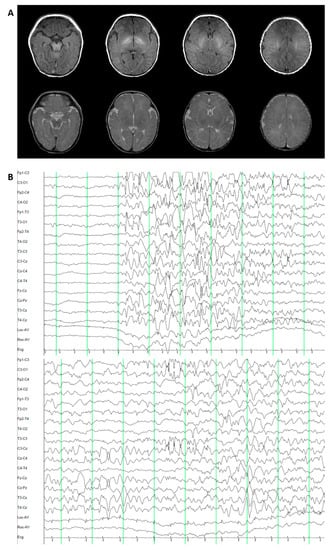

3.1.3. Patient 3. Epileptic Encephalopathy 47 (OMIM 617166)

3.2.3. Patient 3. Epileptic Encephalopathy 47 (OMIM 617166)

3.3.3. Patient 3. Epileptic Encephalopathy 47 (OMIM 617166)